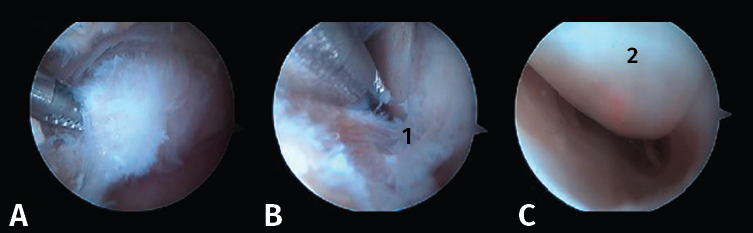

Figura 6. A y B: liberación del retináculo del flexor hallucis longus (FHL) (1); C: evaluación del interior de la vaina del FHL (2).

- Tercer paso. El sinoviotomo se gira ahora para que la ventana vuelva a mirar la cara medial del PPA. En este momento, el tendón FHL permanece medial al sinoviotomo y opuesto a su ventana. Podemos así seccionar el retináculo del FHL con el sinoviotomo o mediante una pinza de tipo basket (Figuras 6 A, B y C).

- Cuarto paso: quitar el LACP de la parte inferior del PPA para completar su liberación (Figura 7 A y B).

Figura 7. A: resección del ligamento astrágalo-calcáneo posterior (LACP) (1) en la parte inferior del proceso posterolateral del astrágalo (PPA); B: PPA (2) después de la resección completa de los ligamentos circundantes.